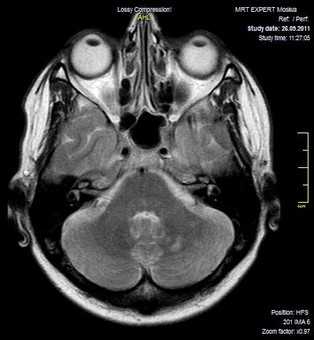

Как выглядит снимок МРТ головного мозга

Классический пример МРТ снимков головного мозга показан на рисунках ниже. Магнитно-резонансная томография выполняется в поперечной (или аксиальной - рисунок снизу) и продольной (или сагиттальной — рисунок сверху) плоскостях.

Исследование выполняется в нескольких режимах. Основные из них Т1 и Т2. Изображения, полученные в данных режимах, часто также называют Т1-взвешенными или Т2-взвешенными снимками. Изображения, показанные выше, сделаны в Т1-режиме.

Главное отличие этих режимов - в том, как на снимках отображается жидкость и воздух. В Т1 режиме ткани, содержащие большое количество воды, имеют более темную окраску, в то время как в Т2 режиме они яркие, светлые. Это легко понять, посмотрев на снимки выше - глазные яблоки визуализируются в виде светлых парных округлых образований с одной стороны яркие и светлые, с другой - темные. Следовательно, снимок справа сделан в Т1 режиме, снимок слева - в Т2. Также существует разница в том, как в этих режимах отображается серое вещество головного мозга. В Т2 режиме оно светлее, чем белое вещество.